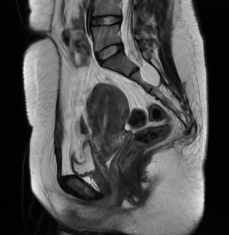

盆腔增強(qiáng)核磁: